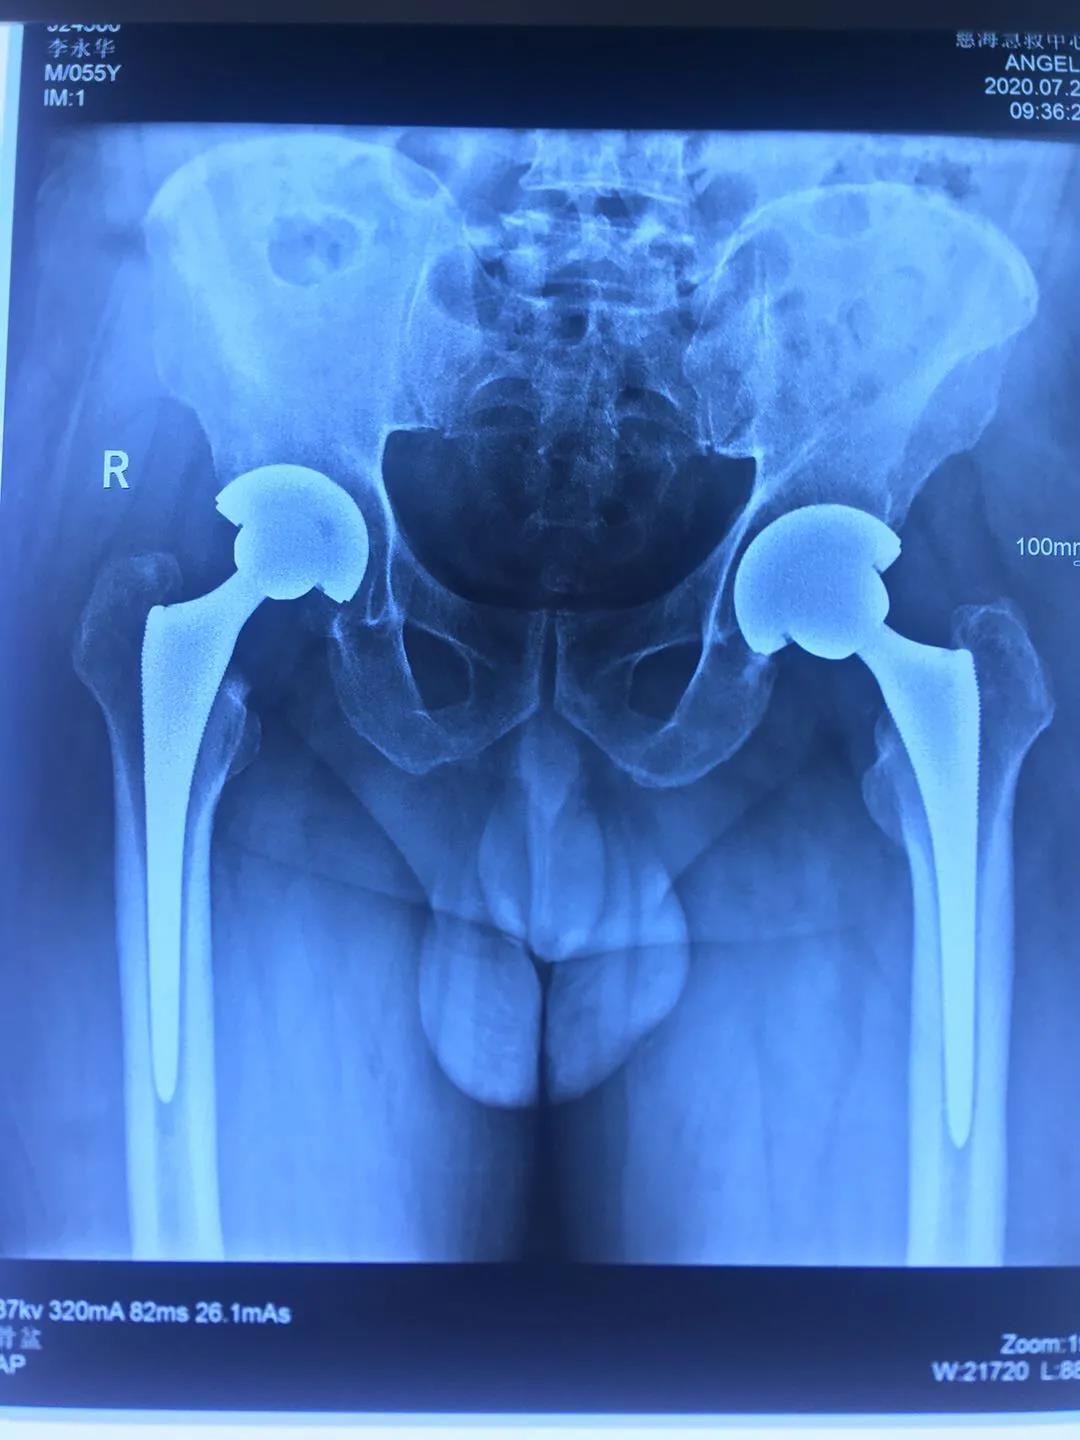

患者一年前雙側(cè)髖疼痛,到骨科就診,確診為股骨頭壞死,由于左髖關(guān)節(jié)痛疼較重給予行左髖關(guān)節(jié)置換,術(shù)后恢復(fù)良好。今年右髖關(guān)節(jié)痛疼加重再次住院,入院后完善相關(guān)檢查,根據(jù)患者病情,征得患者及家屬同意,順利施行了右髖關(guān)節(jié)置換術(shù),術(shù)前片子提示患者骨盆傾斜較重,術(shù)前評(píng)估設(shè)計(jì)術(shù)中假體植入角度,術(shù)后完美恢復(fù)雙下肢長(zhǎng)度與雙側(cè)髖關(guān)節(jié)旋轉(zhuǎn)中心,患者非常滿(mǎn)意,目前患者情況良好,已出院。

術(shù)后復(fù)查拍片